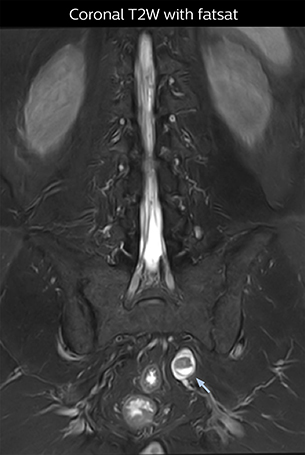

“For example, in sagittal images, when the presence of fat is observed in the intervertebral foramen, it suggests that there is a margin around the nerve. Similarly, the absence of fat indicates that the nerve is being compressed. So, we used to deduce nerve compression indirectly. With NerveVIEW, however, we can observe the condition of the nerves directly, regardless of the presence or absence of fat. We always prefer such direct observation of anatomy over having to make an inference about it.”

“Although symptoms of typical disc herniation and atypical hernia are very similar, the actual site of herniation is different. It is therefore important to characterize the nerve’s condition both inside and outside of the intervertebral foramina. “Conversely, if we see no abnormality in NerveVIEW, we can assume at least that there is no severe condition that requires surgery. Like this, it can help us avoid unnecessary surgery. NerveVIEW can have a tremendous impact in this way.”

“NerveVIEW is really useful for those cases where a nerve disorder is strongly suspected based on the clinical examination but our regular MRI images do not show any findings. These atypical herniations and spinal canal stenosis, occurring in 5% to 15% of the total lumbar herniation/stenosis cases are our main target when using NerveVIEW,” says Dr. Yabuki.